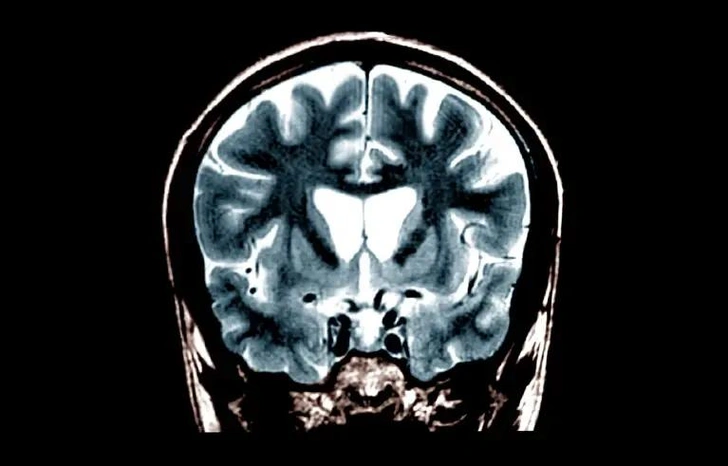

Однократное применение генной терапии может значительно замедлить прогрессирование болезни Хантингтона, потенциально открывая путь к первому в истории лечению, способному изменить течение этого редкого наследственного заболевания головного мозга.

В ходе небольшого исследования с участием 29 человек, у которых наблюдались ранние стадии деменции, связанной с болезнью Хантингтона, у участников, получивших высокую дозу препарата непосредственно в мозг, течение болезни замедлилось на 75% за три года по сравнению с контрольной группой.

Для проведения лечения требуется длительная операция, во время которой врачи с помощью магнитно-резонансной томографии точно вводят канюлю через небольшие отверстия в черепе. Затем препарат медленно вводится в полосатое тело — часть мозга, которая первой и сильнее всего страдает от болезни Хантингтона.